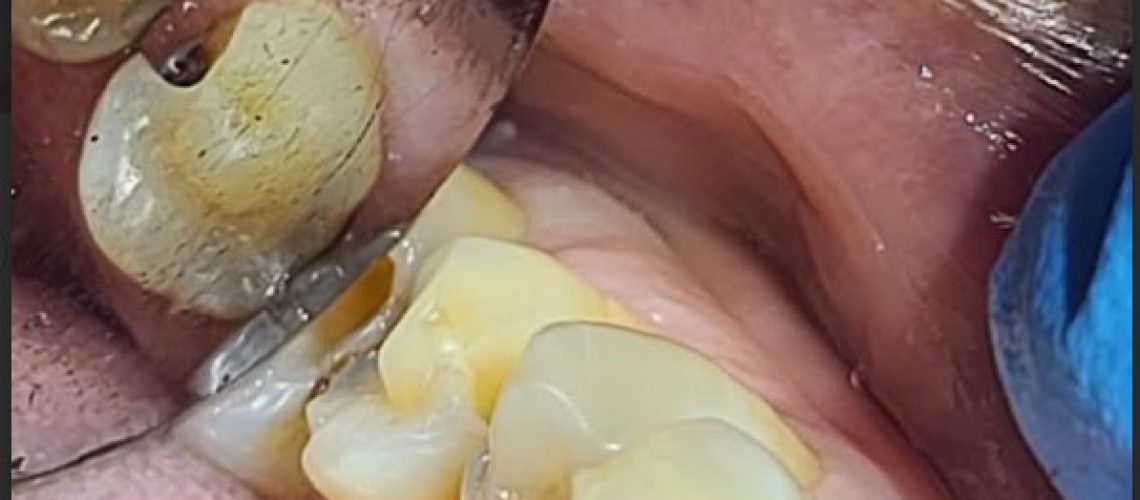

cracked tooth treatment

A cracked or broken tooth can cause pain, sensitivity, and lead to more serious dental issues if not treated promptly. At Polaris Dental Brampton, we provide compassionate, professional care for patients dealing with cracked teeth—including refugee claimants covered under the Interim Federal Health Program (IFHP).

Depending on the severity and location of the crack, our dentists may recommend:

• Dental bonding or dental fillings to seal small cracks

• Dental crowns to restore and protect damaged teeth

• Root canal therapy if the crack has reached the tooth’s pulp

• Tooth extraction, in cases where the damage is beyond repair